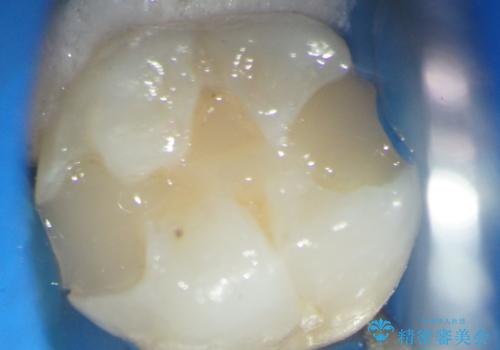

X線検査により外から見てもわからない虫歯が認められたので、マイクロスコープ下で丁寧かつ徹底的に虫歯を除去しセラミックインレーによる修復を計画します。

マイクロスコープを用いることで歯の微細な硬さや虫歯の広がりをすみずみまで精査することができます。

しっかりと虫歯を取り除き、精密なインレーを装着することで虫歯の再発を防ぎ長期的な予後を期待できる環境を整えます。